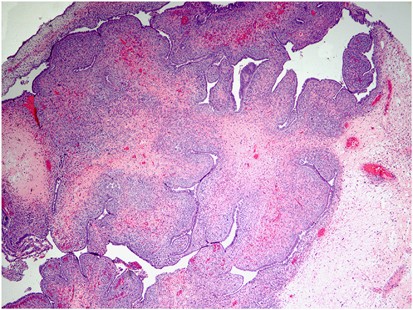

Histologically, the mixed nature of the tumour is exemplified by the presence of both epithelial and stromal elements, the latter predominating. At low power magnification, the tumour often has a phyllodes-like (leaf-like or club-like) architecture (Figure 7). The epithelial elements usually consist of glands, which may be dilated or slit-like with a phyllodes-like appearance, lined by cuboidal or low columnar cells. In most cases, the epithelium is endometrioid and resembles proliferative endometrium, although ciliated, mucinous and squamous epithelium may also be seen. Uncommonly, the epithelial component exhibits glandular complexity resembling atypical hyperplasia/endometrial intraepithelial neoplasia or carcinoma. The latter is usually a low-grade endometrioid carcinoma.28 The stromal component, which is typically low grade, is composed of spindled and/or round cells with scant cytoplasm, but rarely can be high grade. Intraglandular protrusions of stroma and the manner in which the stromal cells, which often resemble endometrial stromal cells, concentrate around or beneath the glandular elements (‘periglandular cuffing’) are characteristic (Figure 8). The ‘cuffing’ may be very thin (and thus overlooked) but is where nuclear atypia and mitotic activity are typically found (Figure 9). Although a mitotic rate of ≥2 per 10 high power fields (HPFs) is often seen, some tumours have a lower mitotic rate and should be diagnosed as adenosarcoma if the tumour has the characteristic aforementioned features as reflected in the 2014 WHO classification.1